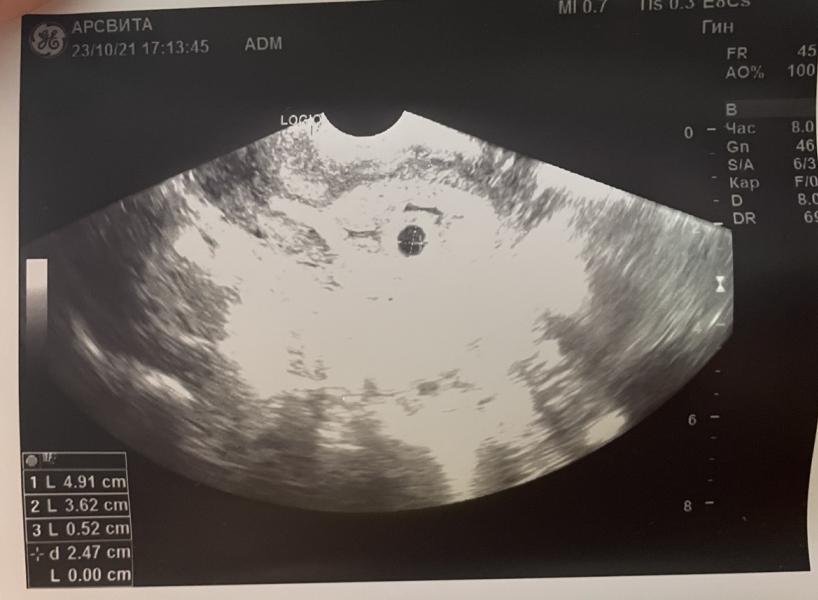

Пошла я сама в 4 недели 4 дня (23 октября) на узи в платную, чтобы исключить внематочную (боли слева внизу были). Плодное яйцо в матке, фух..но там пока ничего не видно 🙈 и киста огромная в левом яичнике, вот это то и болит 🤭🙁 и назначили дюфастон.

0.52 см размер плодного яйца у вас ?

Тогда срок 5 нед 2 дня

@epugacheva, если до 5 мм на узи ПЯ - то срок был 5 н 1 день (3 н 1 д - эмбриональный) - 23 октября по узи))) И если цикл от 21.09, то Овуляция была у вас 1 октября, отсчитайте назад и посчитайте по календарю, овуляция была на 11 дц. И всё у вас хорошо. ХГЧ может чуток высоковат, но это вполне может быть нормой вашего организма. Следите за динамикой каждые 2 суток